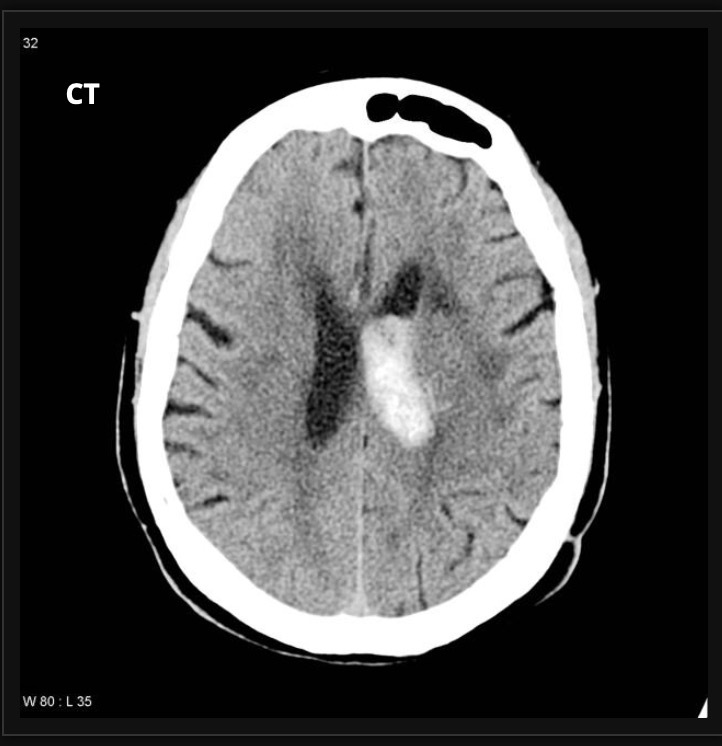

what does this CT scan show?

A

hyperdense haemorrhagic stroke